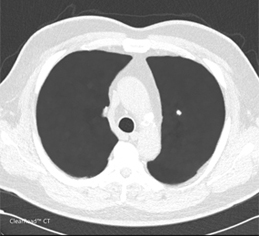

| Clearread CT 人工智慧電腦斷層肺結節分析判讀系統 | | ClearRead CT是一種電腦輔助檢測系統,用於識別和標記注意區域(Regions of Interest,ROI)。ClearRead CT系統適用於所有結節類型,包括實質(solid)、非實質(sub-solid)和毛玻璃樣(ground glass)結節,其尺寸介於5mm到30 mm之間。本系統僅限於每個CT系列(CT series)標記被視為值得檢查的5個 ROI。ClearRead CT的使用可以減少疏漏錯誤。系統的比較元件允許ROI與先前掃描的時間先後比較,並提供隨時間的體積變化。 |  |